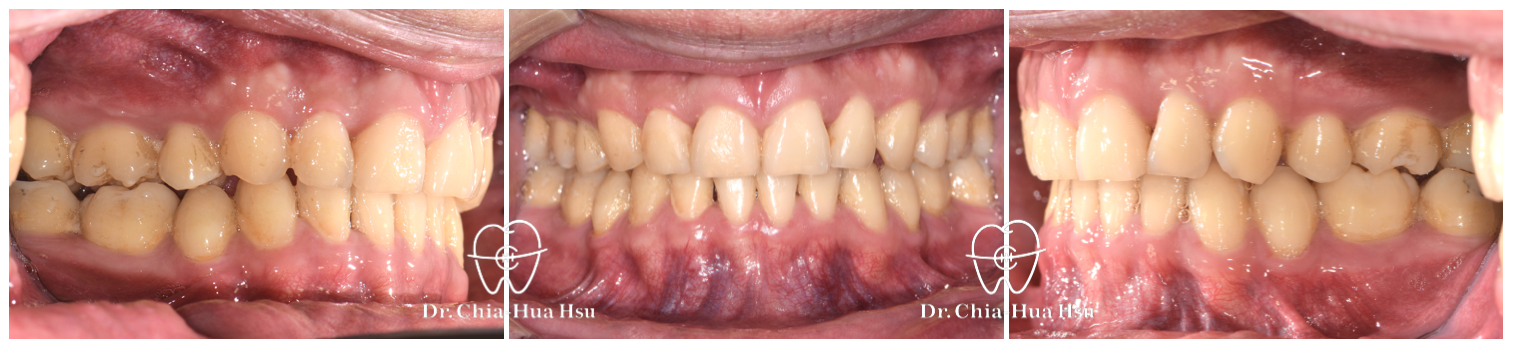

治療前

治療後

• 治療方式:使用傳統金屬矯正器,合併正顎手術(雙顎),以手術方式將下顎骨前移改善呼吸道與外觀。

• 治療結果:齒列排齊,睡眠呼吸中止症改善許多,臉型變長、下巴輪廓也較明顯。